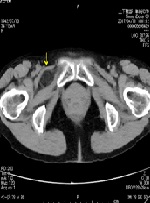

Laparoscopic Transabdominal Preperitoneal Repair for Recurrent Obturator Hernia: A Case Report